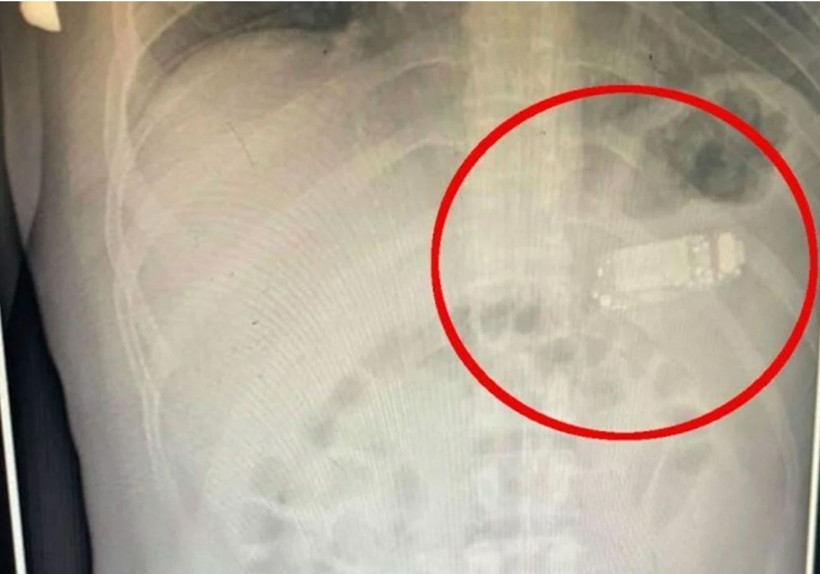

Kosova'nın başkenti Piriştine'de ilginç bir olay yaşandı. Doktorlar 33 yaşındaki bir erkek hastanın midesinden, Nokia 3310'unun yenilenmiş versiyonunu ameliyatla çıkardı. Uzmanlar, özellikle telefonunun bataryasından kaynaklanan kimyasalların yutulması durumunda ölümcül olacağını vurguladı.

Midesinde 4 gün kaldı

Güneydoğu Avrupa'da denize kıyısı olmayan bir ülke olan Kosova'nın başkenti Priştine'de doktorlar, Nokia 3310 model bir cep telefonunu yutan adamı ameliyat etti. Telefonun adı açıklamayan adamın midesinde dört gün kaldığı belirtildi. Başarılı operasyonu gerçekleştiren sağlık ekibinin başındaki doktor Skender Teljaku, adamın midesinden çıkarılan telefonun fotoğrafları ile röntgen ve endoskop görüntülerini Facebook'ta yayınladı.

Teljaku yaptığı açıklamada, tıbbi ekibin telefonu mideyi kesmeden, endoskop olarak bilinen özel cihazlar kullanarak üç ayrı parçaya ayırmayı başardığını söyledi. Teljaku, ayrıca yaklaşık iki saat süren işlem sırasında "herhangi bir komplikasyon" yaşanmadığını sözlerine ekledi.

Bununla birlikte 33 yaşındaki  adamın telefonu yuttuktan sonra yaşadığı acı nedeniyle Kosova'nın başkentindeki hastaneye gitmeye karar verdiği aktarıldı. Teljaku, özellikle bataryanın en tehlikeli parçası olduğunu, patlayarak hayatı potansiyel olarak tehlikede olan adamın bağırsaklarına kimyasal salabileceğini söyledi.